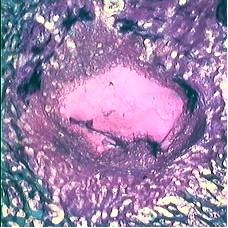

Rivestimento di materiali da impianto per fissazione esterna ed interna con materiali bioattivi per favorire i processi di osteointegrazione in osso sano ed osteopenico - In chirurgia ortopedica ricostruttiva vengono impiegati numerosi mezzi di fissazione che oltre ad essere biocompatibili devono osteointegrarsi meccanicamente e biologicamente con il tessuto osseo. immagine decorativaLa superficie degli impianti, la stabilità primaria, la risposta precoce ossea all’impianto, la fissazione biologica, il carico meccanico ed  i processi di rimodellamento sono i principali fattori che influenzano l’osteointegrazione degli impianti. Le complicanze legate alla scarsa osteointegrazione degli impianti ortopedici per la fissazione delle fratture sono più frequenti quando i biomateriali vengono impiantati in osso osteoporotico a causa di deficit strutturali, biomeccanici e biologici legati all’invecchiamento ed alla patologia stessa. Per questi motivi, sono di grande interesse i biomateriali metallici con superfici modificate al fine di stimolare la risposta cellulare e tessutale agli impianti e, di conseguenza, il successo della chirurgia ricostruttiva. Solitamente vengono impiegati rivestimenti di materiali ceramici o di titanio a morfologia e biochimica tale da stimolare la crescita ed il rimodellamento osseo. La valutazione preclinica di questi dispositivi richiede l’impiego di modelli sperimentali anche di tipo patologico.